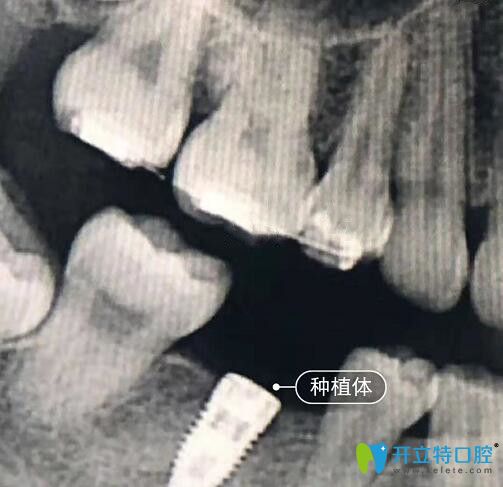

我在<!--<i data=20240703-sp></i>-->億大口腔做種植牙CT片

億大口腔的張睿醫(yī)生不愧是原的種植醫(yī)生,種植牙技術確實不錯,而且服務也很貼心,術后會定期回訪、提醒復診等。所以,還在糾結“種植牙哪家醫(yī)院好?”的朋友們,可以到億大口腔體驗,既能享受到與醫(yī)生同步的技術,還免去了排隊的麻煩!